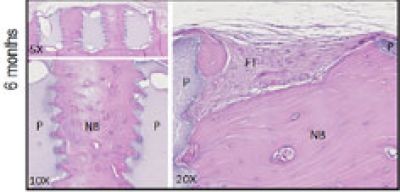

The combination of the osteoconductive and osteointegration properties of hydroxyapatite with interconnected pores promotes the colonization of the bone graft by blood vessels (Fig. 1).

A pre-clinical study showed that the advanced porosity design of MyBone leads to 5 times faster osteointegration than conventional porosity designs [4].

Fig 1. Descriptive histology at 3 and 6 months after hydroxyapatite bone graft implantation on rat calvaria focused on the inner pore area. BV, blood vessels; FT, fibrous connective tissue and black arrows show giant cells; NB, newly formed bone; P, pellet.